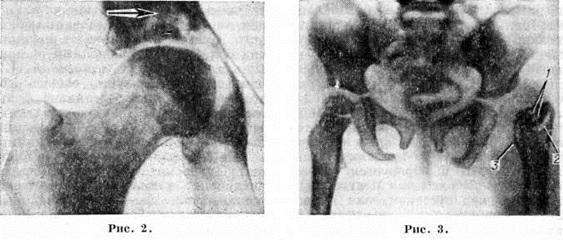

Рис. 2. Рентгенограмма правого тазобедренного сустава: специфический (туберкулёзный) остит вертлужной впадины (указан стрелкой), выраженный остеопороз шейки и большого вертела бедренной кости.

Рис. 3. Рентгенограмма таза и тазобедренных суставов ребёнка при левостороннем гнойном коксите: головка и шейка левой бедренной кости разрушены, в сохранившейся проксимальной части бедренной кости (2) видны два деструктивных очага (1), они окружены ободком склеротического уплотнения костной ткани, на бедренной кости значительные периостальные наслоения (3); уплотнение мягких тканей левого бедра.

Характерным для рентгенологическое картины Коксит является сужение суставной щели и деструкция суставных поверхностей (рисунок 2). При накоплении в полости сустава воспалительного экссудата на рентгенограмме обнаруживают незначительное или отчётливо выраженное смещение головки бедренной кости кнаружи и несколько кверху. Наличие деструктивных очагов в костях сустава, чаще наблюдаемых у мест прикрепления суставной капсулы, указывает на развитие активного воспалительного процесса в тазобедренном суставе. Такие очаги при Коксит могут наблюдаться не только в шейке и головке бедренной кости, но и в подвздошной, седалищной и лобковой костях,

В начальной стадии костного воспалительного процесса как при неспецифических, так и при специфических Коксит деструктивный очаг имеет небольшие размеры и нечёткие контуры. Поэтому для обнаружения подобных очагов рекомендуется томографическое исследование. В отличие от туберкулёзного Коксит, при неспецифическом Коксит деструктивные очаги и полости обычно множественны, имеют чётко обозначенные контуры, окружены склерозированным костным ободком (рисунок 3).